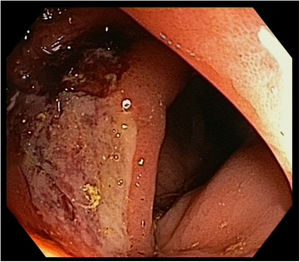

En una tomografía computarizada de control realizada 10meses después del diagnóstico se objetivó un engrosamiento mural del colon ascendente (fig. 1). Se realizó una colonoscopia, observándose en colon derecho una úlcera superficial de aspecto inespecífico (fig. 2). La histopatología fue compatible con metástasis colónica de carcinoma escamoso pulmonar (fig. 3).